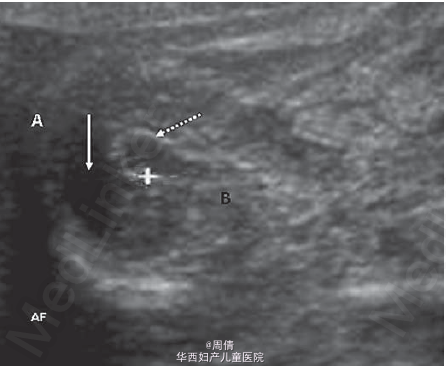

30岁女性,孕30+5周,因为12小时胎动减少入院

超声提示胎动减少,少量腹水,扩大的胆囊和扩张的小肠 多普勒提示胎盘缺氧,但和胎盘的血管没有关系 羊膜腔穿刺术提示羊膜内感染,G(+),糖减少,多核细胞增多